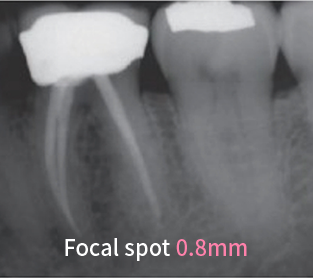

ЧЕТКОЕ ИЗОБРАЖЕНИЕ

Фокусное пятно размером 0,4 мм обеспечивает качественное изображение для стоматологов